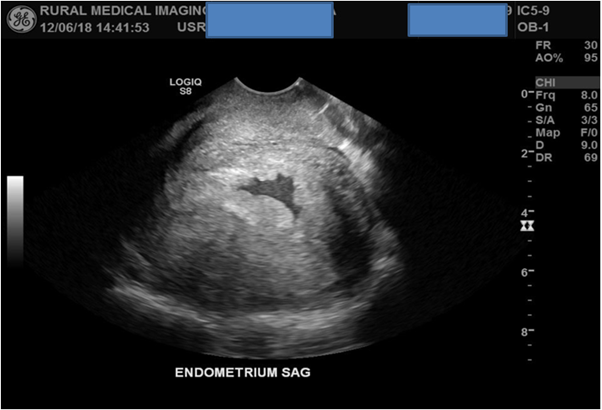

TVS was started with the uterus in the longitudinal plane and the same “sweeping” scan method consistent with that of TAS was used. Also included in the scan was an assessment of the cervix in both longitudinal and transverse planes which found it to be of normal appearance. TVS detected an irregular shaped anechoic collection of fluid within the intrauterine cavity measuring 20x6x18mm with a volume of 1.12ml. This fluid was not detected using TAS, again no obvious GS or IUP was detected.

Figure 4: TVS detects an irregular shaped collection of anechoic fluid within the intrauterine cavity.